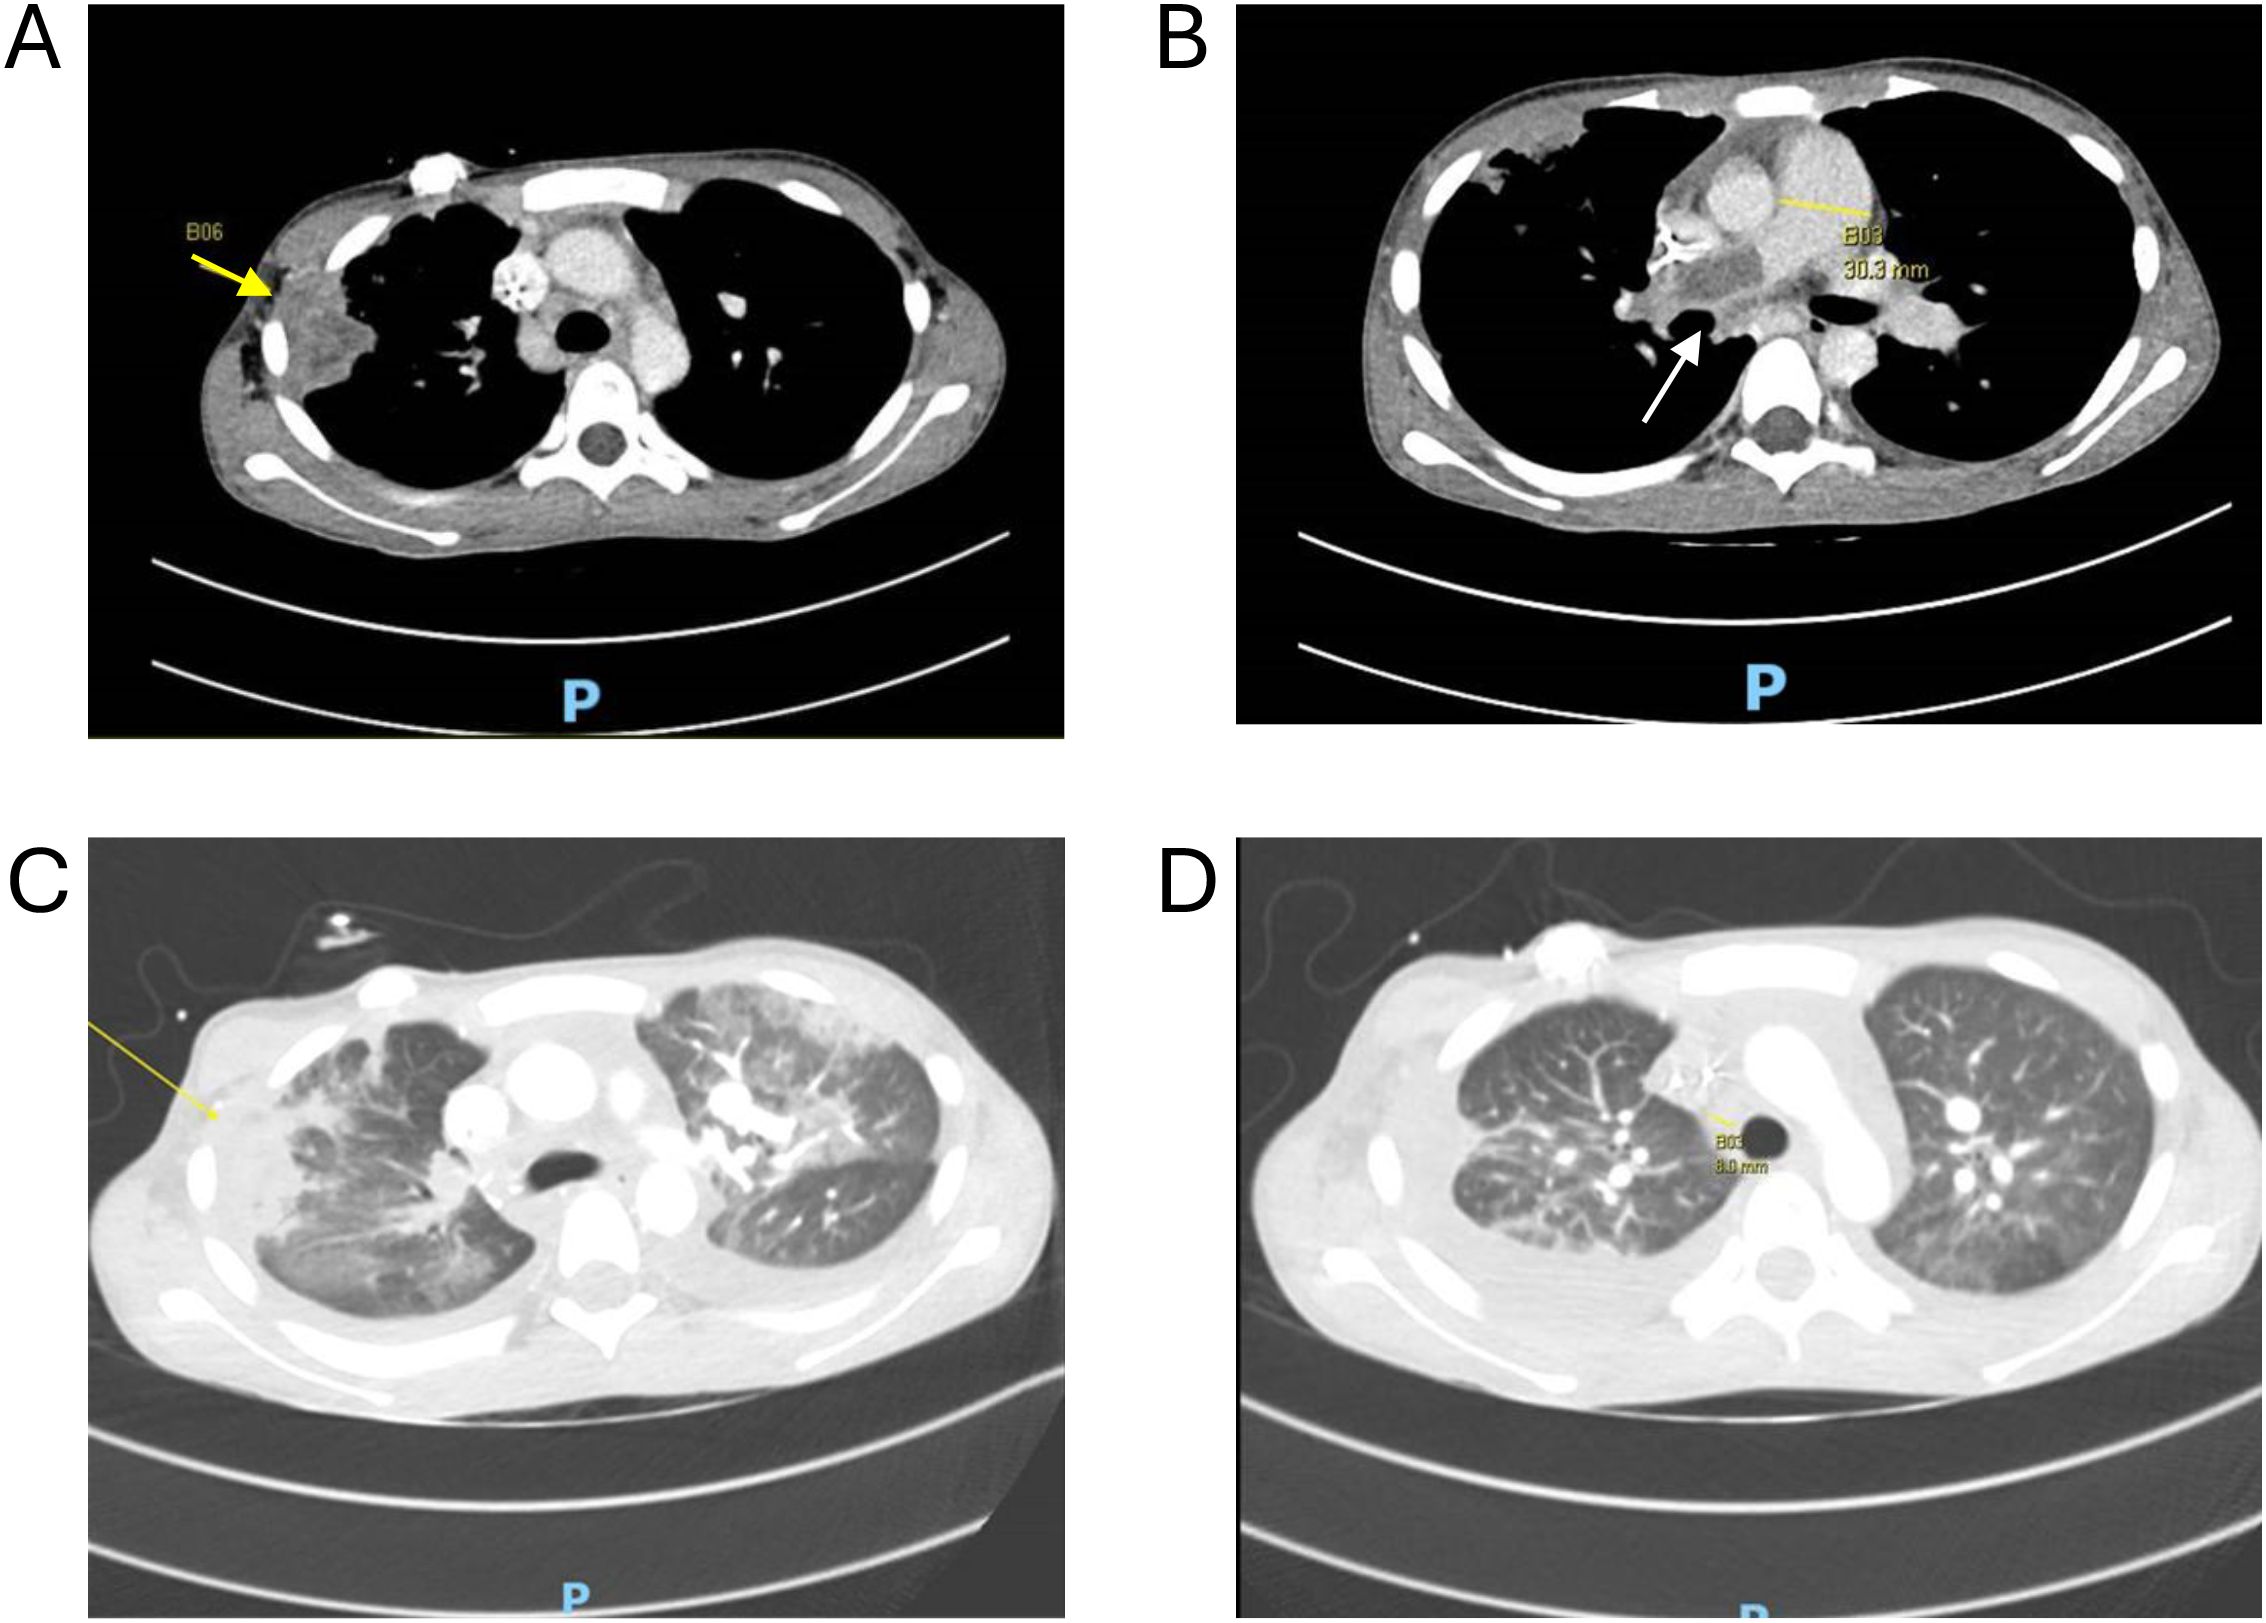

Patient 5 had AML with FLT3-ITD, relapsing within 4 months after consolidative HSCT (busulfan–cyclophosphamide conditioning, matched sibling donor). The AML was refractory to azacitidine/venetoclax reinduction and complicated by angio-invasive pulmonary mucormycosis (Rhizopus) involving the right main pulmonary artery, left lower lobar artery, right chest wall, and both lung extensively (Figure 1). After referral, mucormycosis was treated with thrombectomies, isavuconazole, and ambisome, while leukemia was treated with gilteritinib, venetoclax, and azacitidine. At vaccine transplant, he still had extensive pulmonary disease and ~50% circulating blasts.

Figure 1

Angioinvasive pulmonary mucormycosis. (A) Peripheral consolidation with pleural and chest wall invasion (yellow arrow). (B) Extensive pulmonary embolus (white arrow) expanding the right main pulmonary artery (30.3mm) extending into the right lobar, segmental and subsegmental pulmonary arteries. (C) Extensive ground glass opacities scattered throughout both lungs. (D) Interval resolution one month after vaccine transplantation.